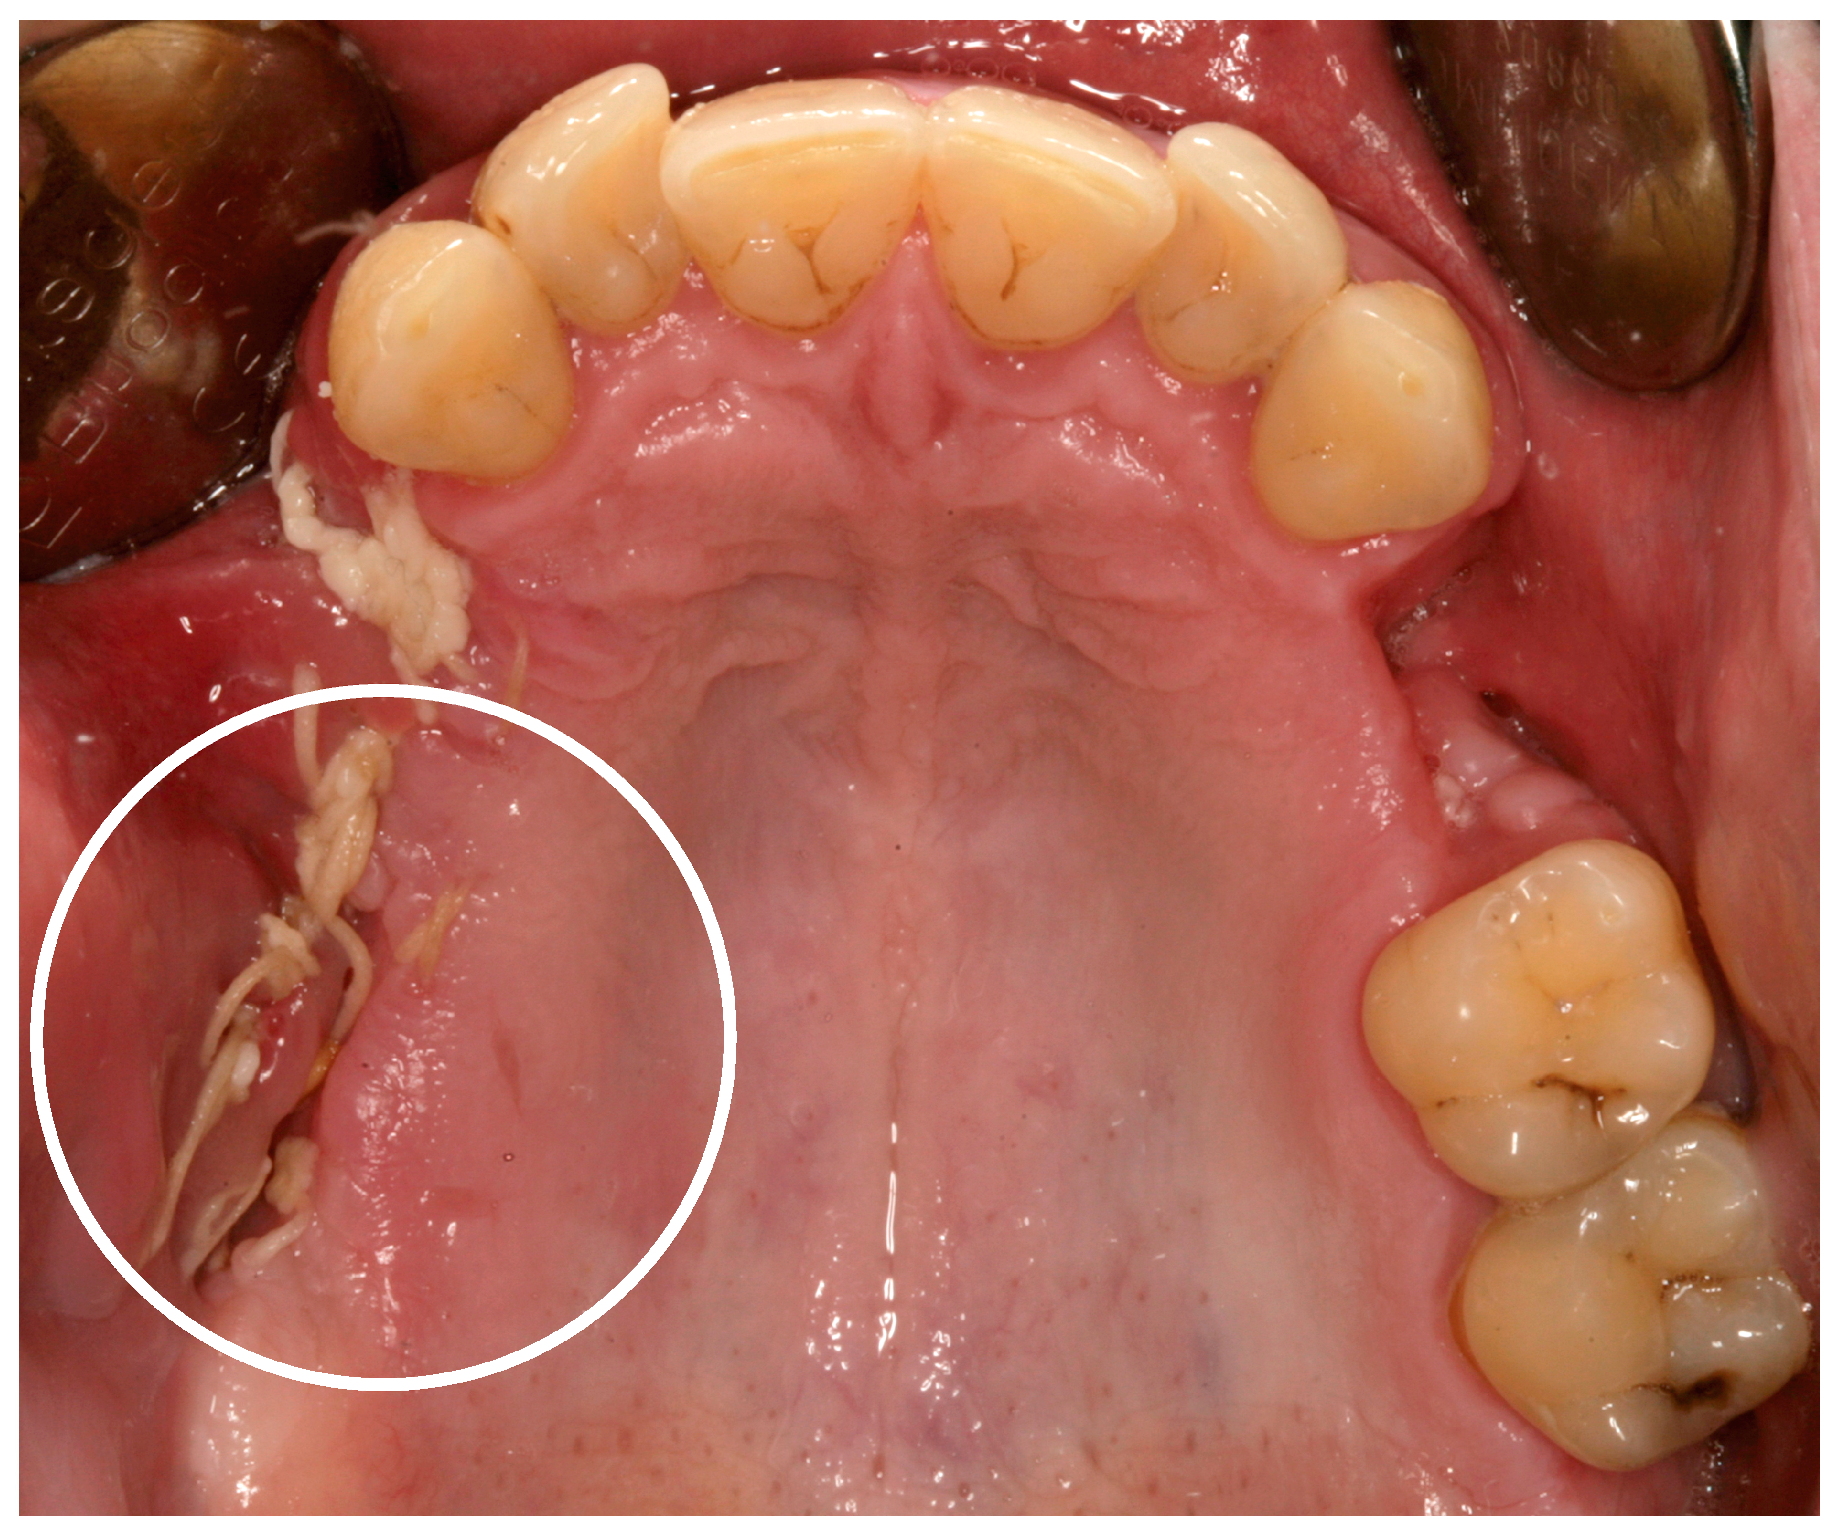

Figure 2.

Twenty-one days postoperatively the wound bed still looked fragile and not “stage-related” (white circle). After the removal of the sutures, wound bed has immediately ruptured again [9].

In recent years, case reports and studies on osteonecrosis after long-term methamphetamine abuse similar to the medication-related osteonecrosis of the jaws (MRONJ) have been published. Basin et al., reported cases of jaw necrosis in patients after desomorphin abuse in Russia, which has been confirmed by further studies [5,6,7,8]. Recently, Pabst and Werkmeister presented a case report of a young patient (male, 26 years) after four years of “meth” abuse and the development of an extended ONJ in the maxilla after tooth extractions, see Figure 1 and Figure 2 [9]. The patient had no further general diseases or allergies. His patient history was unobtrusive with exception of the “meth” abuse. A surgical wound revision of the affected areas was performed with general anesthesia, including a resection of necrotic bone and a saliva-proof wound closure under antibiotic treatment. The sutures were removed on day 21 postoperatively. To date, regular intraoral soft-tissue conditions can be observed. Further, restorative dentistry has been performed in private practice to restore the remaining teeth [9].